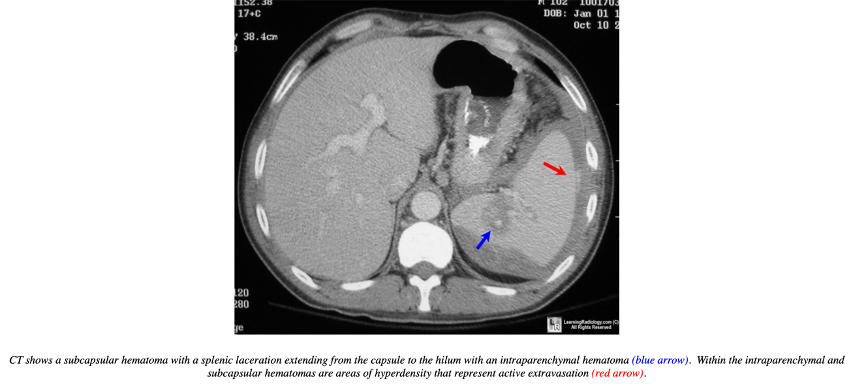

Miltraume:

Q

Diagnose?